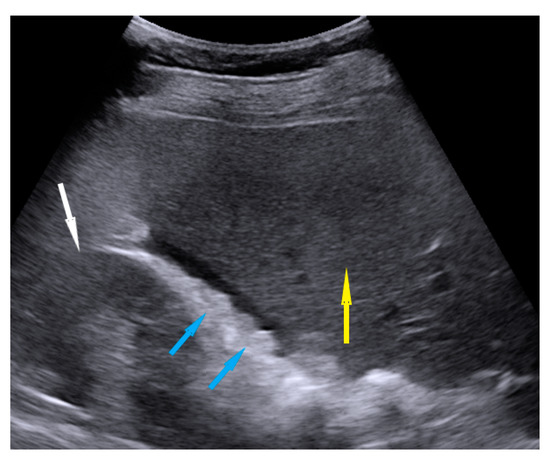

| Spleen, hilum | Presence of nodules or rigid structures in the region of the spleen hilum. | Figure 9 | Video S9 |

| Diaphragm, right | Carcinomatosis manifests as hypoechogenic lesions over the peritoneal surface of the right diaphragm. | Figure 10 | Video S10 |

| Diaphragm, left | Carcinomatosis manifests as hypoechogenic lesions over the peritoneal surface of the left diaphragm. | Figure 11 | Video S11 |